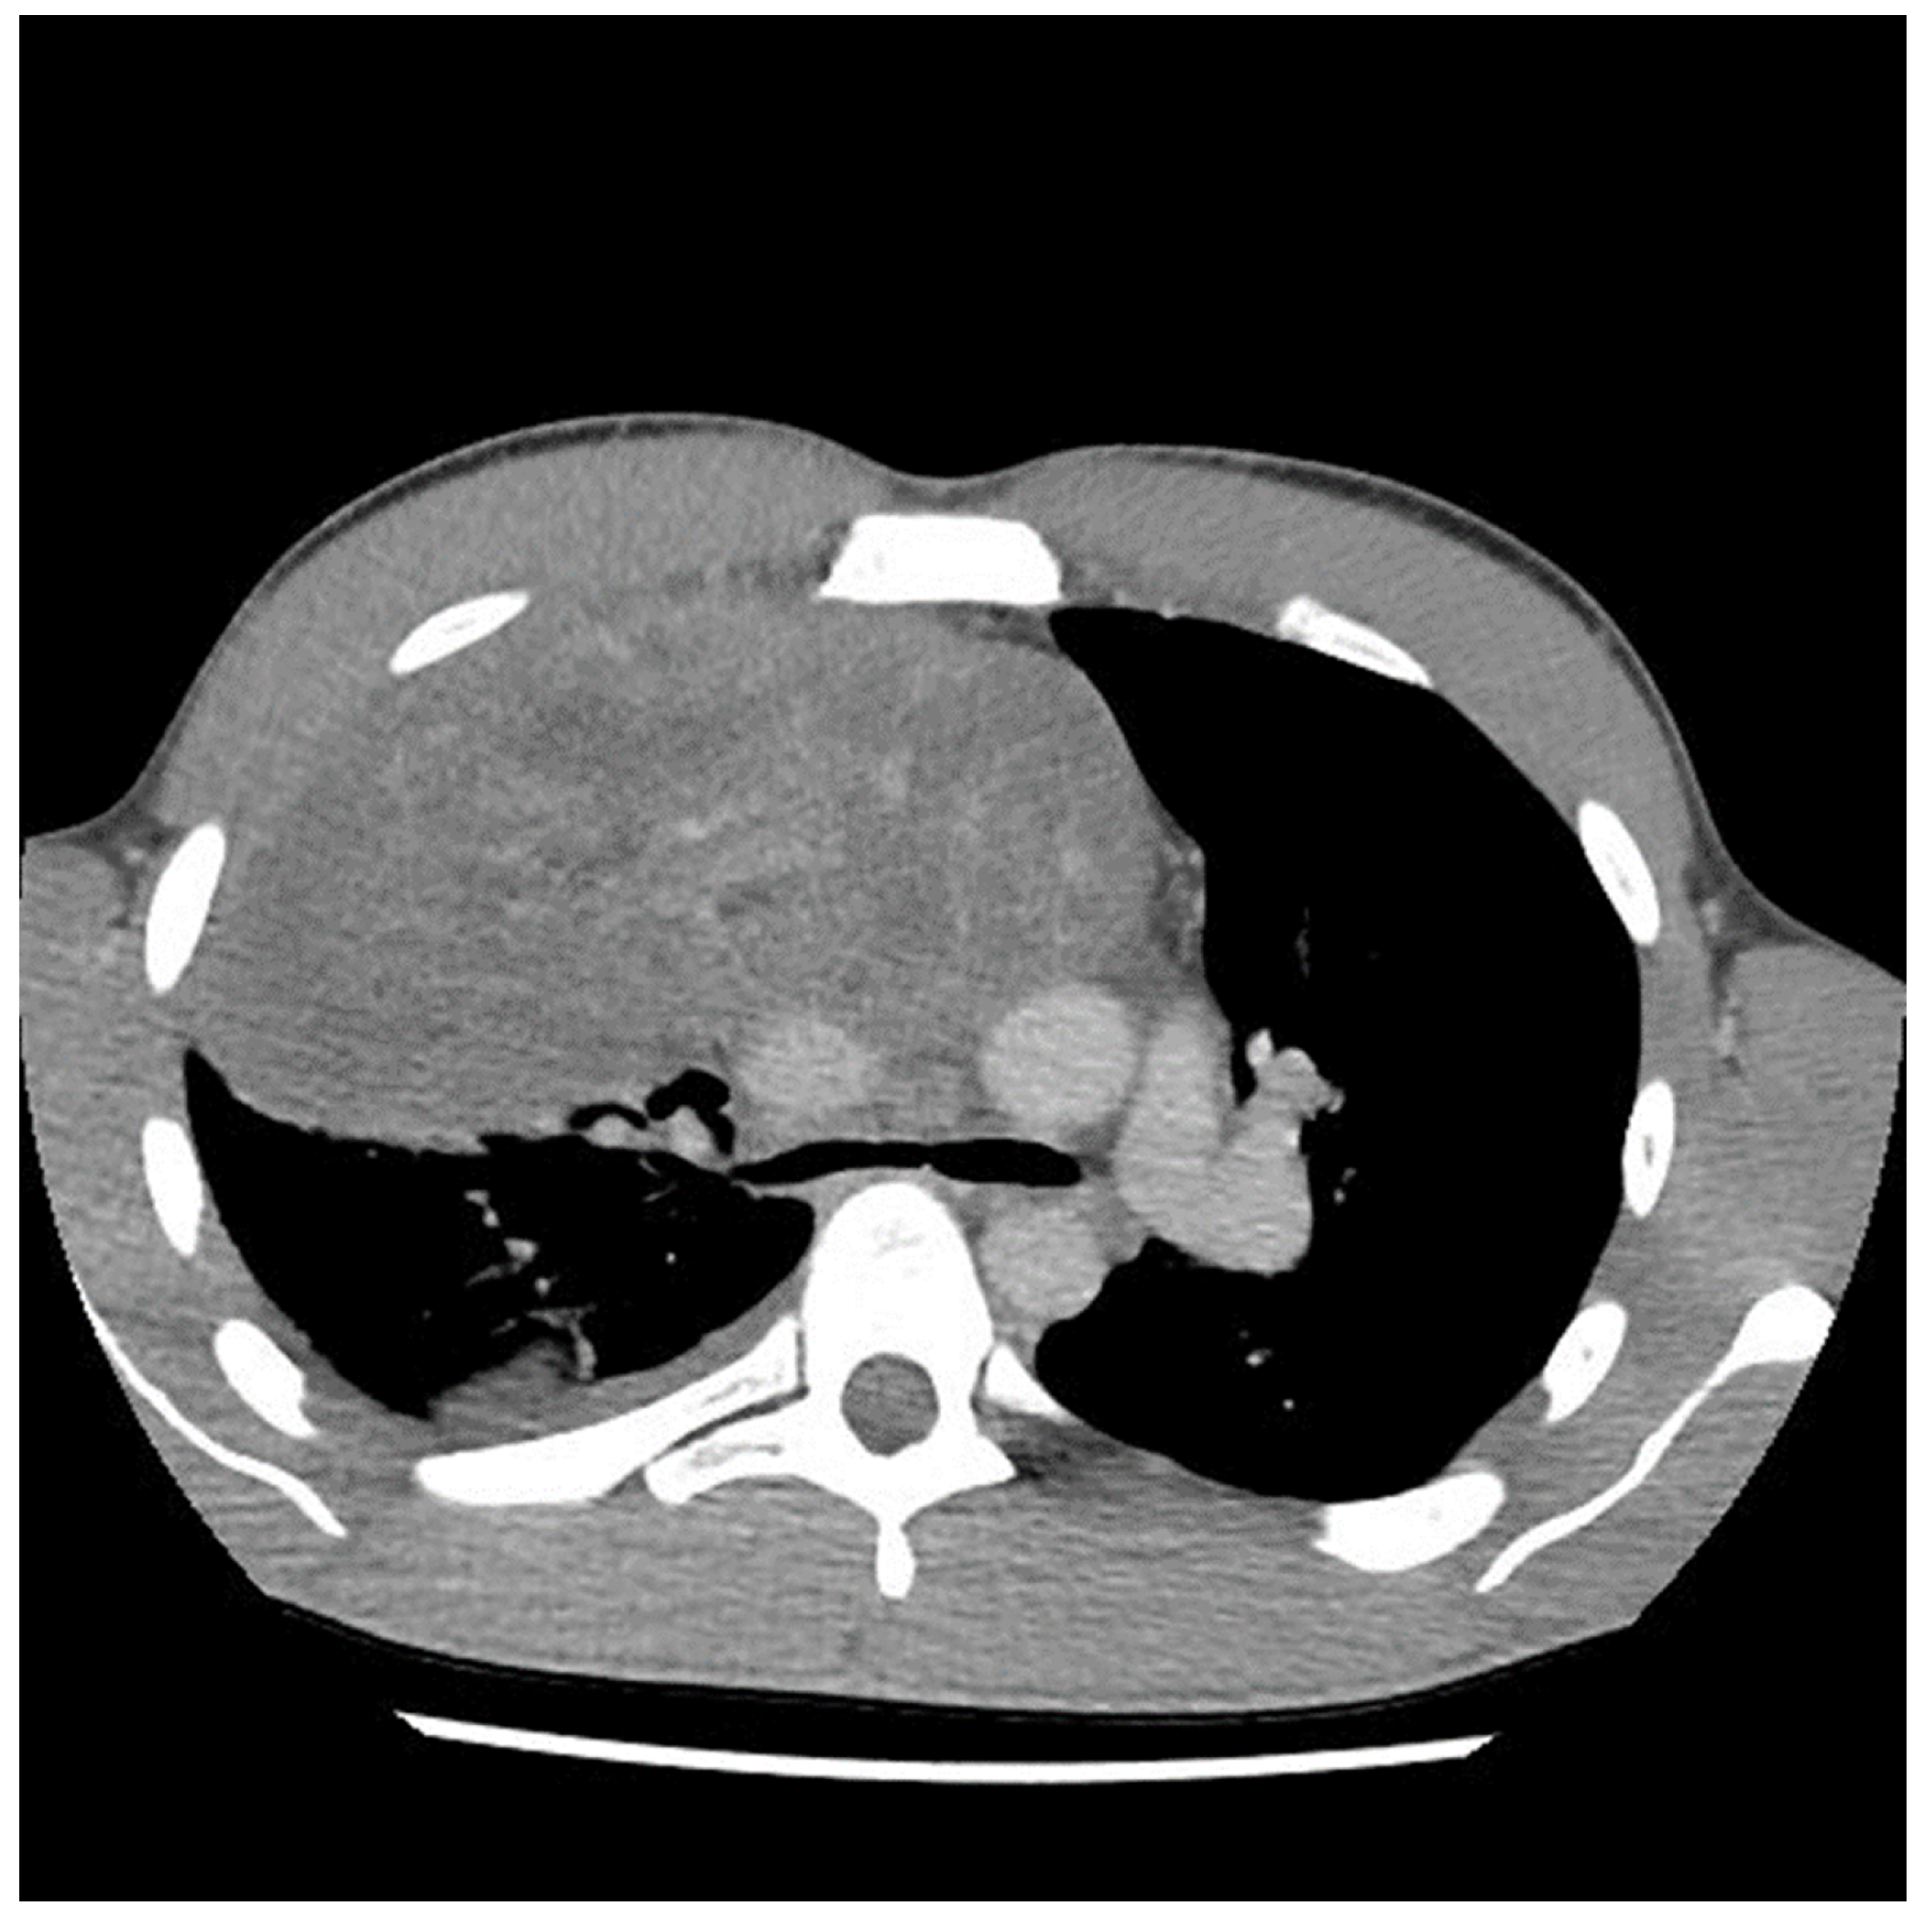

A 29-year-old male with no previous medical history presented to the emergency department in May 2021 with symptoms of acute appendicitis. He was ultimately found to have a large mediastinal mass (Figure 1). A needle biopsy indicated predominantly mature teratomas with some elements of a yolk sac tumor (YST). Biochemical workup revealed an initial alpha fetal protein (AFP) level of 1654.51 ng/mL, and the beta human chorionic gonadotropin (β-HCG) level was slightly elevated at 7.2 (IU/L).

Figure 1.

Computed tomography (CT) scan image of mediastinal mass at the time of initial presentation.

The preoperative CT (Figure 1, Figure 2 and Figure 3) identified the involvement of three critical structures: (1) left subclavian artery, (2) right hilum of the lung and (3) SVC. Interestingly, only the encasement of the SVC was confirmed at the time of the surgery. The tumor enveloped the left subclavian on either side but could be peeled off, allowing preservation of the vessel. The tumor abutted the right hilum of the lung but maintained a potential space, so the lesion could simply be lifted off this region. The mass was densely adherent to the lung parenchyma, which was released with cautery. This resulted in a postoperative air leak, which was resolved with conservative management. The encasement of the SVC was the greatest operative challenge. Because the tumor significantly distorted the anatomy of the heart, the SVC was misidentified at the time of surgery, both by direct inspection and TEE evaluation. In retrospect, the use of adjunct techniques, such as a bubble study or the introduction of a wire under direct visualization, could have been helpful in ascertaining the structure intraoperatively. Transaction would have still been required for en bloc resection, but immediate reconstruction of the vessel would have then been possible.